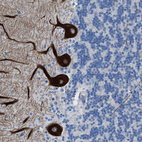

Immunohistochemical staining of human cerebral cortex shows weak to moderate cytoplasmic positivity in neurons.